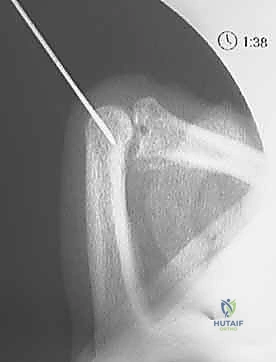

2. K-wire Placement: The Dorsal Blocking Pin

Once you have a stable, concentrically reduced joint, we proceed with placing the K-wire. The principle here is to insert a K-wire into the proximal phalanx, creating a mechanical block that prevents the middle phalanx from hyperextending and re-dislocating dorsally, while still allowing full flexion.

- Choose Your Wire: We'll use a smooth K-wire, typically 0.035-inch or 0.045-inch in diameter. The smaller diameter is often preferred in the digits to minimize bone removal and potential for articular damage, but a 0.045-inch wire offers more rigidity.

- Joint Positioning: Maintain the PIP joint in 90 degrees or more of flexion. This is absolutely critical. Hyperflexion of the joint serves two purposes:

- It ensures the extensor mechanism (central slip) is relaxed and displaced dorsally, minimizing the risk of tethering it with the K-wire.

- It positions the proximal phalanx head optimally for pin insertion, allowing the pin to pass through the dorsal aspect without entering the articular surface.

- Entry Point Selection: Identify the distal, dorsal aspect of the proximal phalanx. The ideal entry point is just proximal to the PIP joint line, slightly off-center (either radially or ulnarly) to avoid the central slip of the extensor tendon. If you place it centrally, you risk tethering the extensor mechanism, which can limit future joint flexion.

Clinical view of K-wire entry point.

* K-wire Insertion Angle: Insert the K-wire percutaneously, aiming in a retrograde direction, approximately 30 degrees off the long axis of the proximal phalanx. The angle is crucial to ensure the pin is within the bone and not crossing the joint.

* Fluoroscopic Guidance (Constant Monitoring):

* Initial Entry: Advance the K-wire slowly with a power drill or by hand. Confirm its entry into the bone of the proximal phalanx on both AP and lateral fluoroscopic views.

* Guidance through Shaft: Guide the wire through the shaft of the proximal phalanx, aiming slightly volar.

* Target Depth: Advance the K-wire until its tip lies just proximal to the articular cartilage of the proximal phalanx head. The tip should not enter the joint space. This is your blocking point.

Fluoroscopic view of K-wire in proximal phalanx (AP).

Fluoroscopic view of K-wire in proximal phalanx (Lateral).

Fluoroscopic view of K-wire in proximal phalanx, demonstrating blocking position.